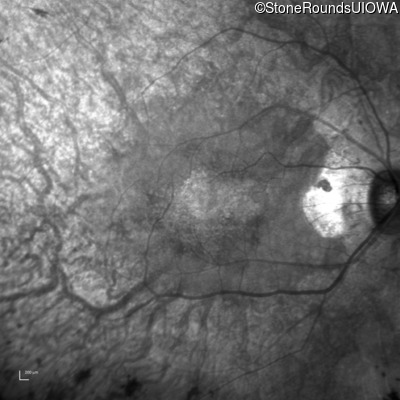

Infrared Fundus Photograph - Right - 20/20

Exemplar